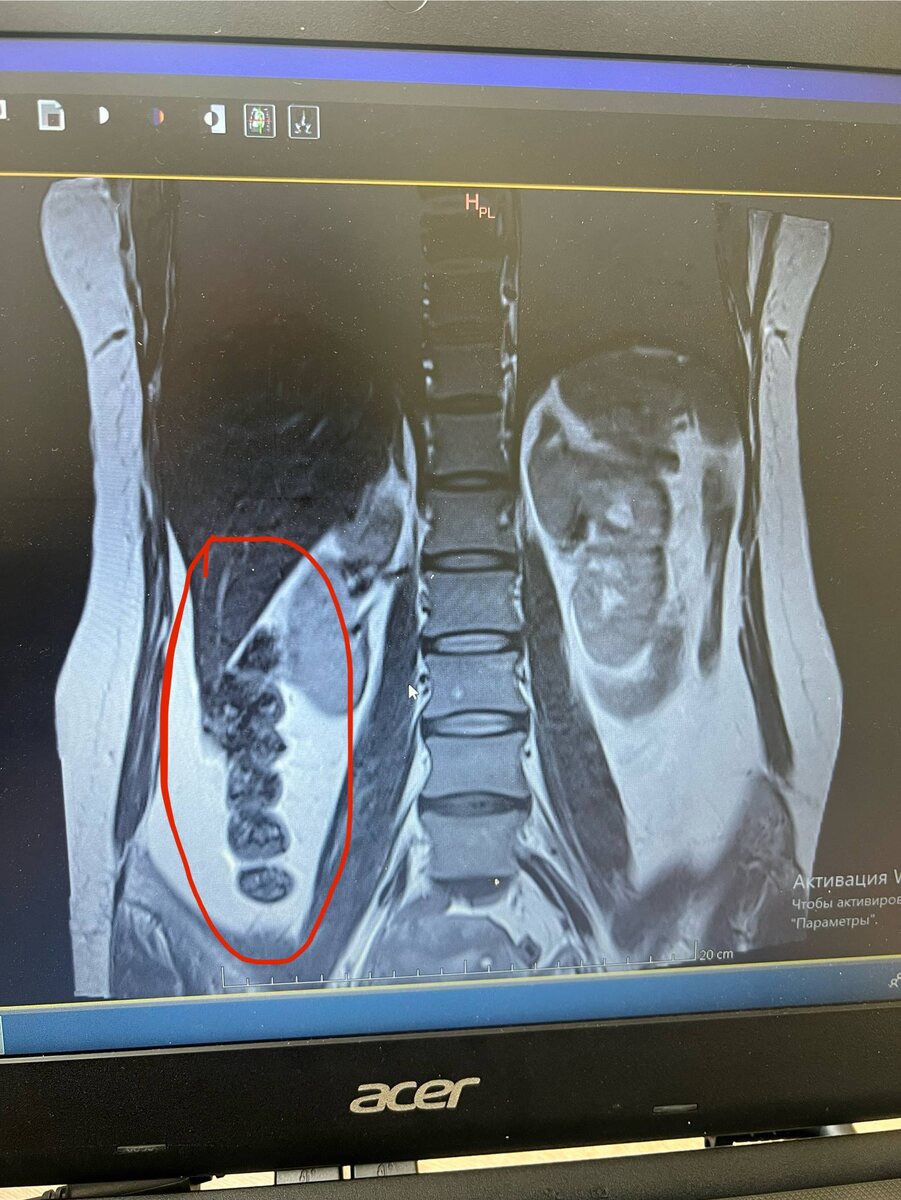

На снимке МРТ (слева на кадре) четко видно восходящую часть кишечника, обычно такое не заметно на МРТ, только отголоски, а также на других снимках просматривается возможная проблема с маткой (вероятно миома)

Чтобы вы понимали в описании к МРТ этих данных нет👎

Итог: скорее всего у пациента воспаление кишечника, которое приводит к сдавливанию почки, а также проблемы репродуктивных органов, а сам позвоночник в неплохом состоянии, за исключением сломанного копчика и местами идет перестройка костной ткани на жировую ( что тоже не есть хорошо)